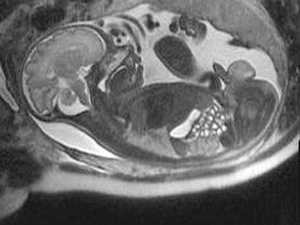

Показанием к проведению МРТ плода являются данные УЗИ, когда была выявлена патология плода, и требуется уточнить характера изменений. МРТ обладает высокой чувствительностью в возможности тканевых характеристик. Результаты МРТ в 55% позволяют получить дополнительную информацию, что, в конечном счете, может повлиять на тактику ведения беременности, определить объем хирургического вмешательства.

Показанием к проведению МРТ плода являются данные УЗИ, когда была выявлена патология плода, и требуется уточнить характера изменений МРТ обладает высокой чувствительностью в возможности тканевых характеристик. Результаты МРТ в 55% позволяют получить дополнительную информацию, что, в конечном счете, может повлиять на тактику ведения беременности, определить объем хирургического вмешательства. Дополнительные данные выявляются в случаях когда, имеющиеся сложные, сочетанные пороки развития не могут быть выявлены при УЗИ, или видны не в полном объеме. МРТ более чувствительный метод в диагностике мальформаций кортикального развития, связанных с нарушением организации и формирования извилин головного мозга, наличия участков гетеротопии и т.д..

Ультразвуковое исследование (УЗИ) есть и всегда будет первым методом мониторинга состояния плода. Но иногда при проведении УЗИ исследуемый анатомический регион или структура по разным причинам плохо видны: например, из-за костной тени, положения плода, ожирения матери или избыточного количества амниотической жидкости. В таких случаях УЗИ дает не совсем ясную картину патологии, поэтому ее значимость для будущего ребенка бывает трудно правильно оценить. Магнитно-резонансная томография (МРТ) позволяет увидеть плод и область интереса методом прямой визуализации и без какого-либо вредного воздействия на плод. Более того, одновременная детальная визуализация патологии центральной нервной системы (ЦНС) и всех остальных структур плода является несомненным преимуществом МРТ. Именно поэтому, подозреваемые по УЗИ изменения являются основным показанием к проведению МРТ плода. Кроме того, МРТ может быть выполнена по желанию матери, особенно, если у нее по какой-либо причине имеется высокий риск формирования патологии у плода.

До недавнего времени основным ограничивающим фактором для широкого использования МРТ являлись движения плода. Сегодня развитие сверхбыстрых МРТ последовательностей позволили решить эту проблему. Современные технологии и аппараты нового поколения позволяют получать изображения менее чем за секунду, выбирать любую плоскость сканирования, в том числе, в кино-режиме. Это способствует ранней диагностике патологии плода, помогает радиологам быть более точными в постановке диагноза, дает возможность акушерам заранее планировать необходимое оперативное лечение и соответствующий постнатальный уход.

Самым распространенным показанием к проведению МРТ плода является патология, выявленная на УЗИ, которая требует уточнения характера изменений. Некоторые сложные сочетанные пороки развития не могут быть выявлены на УЗИ или видны не в полном объеме. Результаты МРТ могут помочь родителям и врачам подготовиться к хирургической операции или к другому лечению вскоре после рождения ребенка или решить вопрос о прерывании беременности по медицинским показаниям. В других случаях, когда подозреваемая на УЗИ патология опровергается в ходе МРТ, процедура может успокоить родителей, и показать, что рассматриваемая проблема несерьезна или вообще не существует.